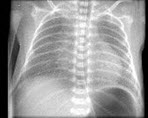

24、单项选择题

女,1天早产儿,呼吸困难、发绀,结合图像,最可能的诊断是()

A.呼吸窘迫综合征

B.新生儿肺炎

C.法洛四联征

D.新生儿支气管炎

E.肺不张